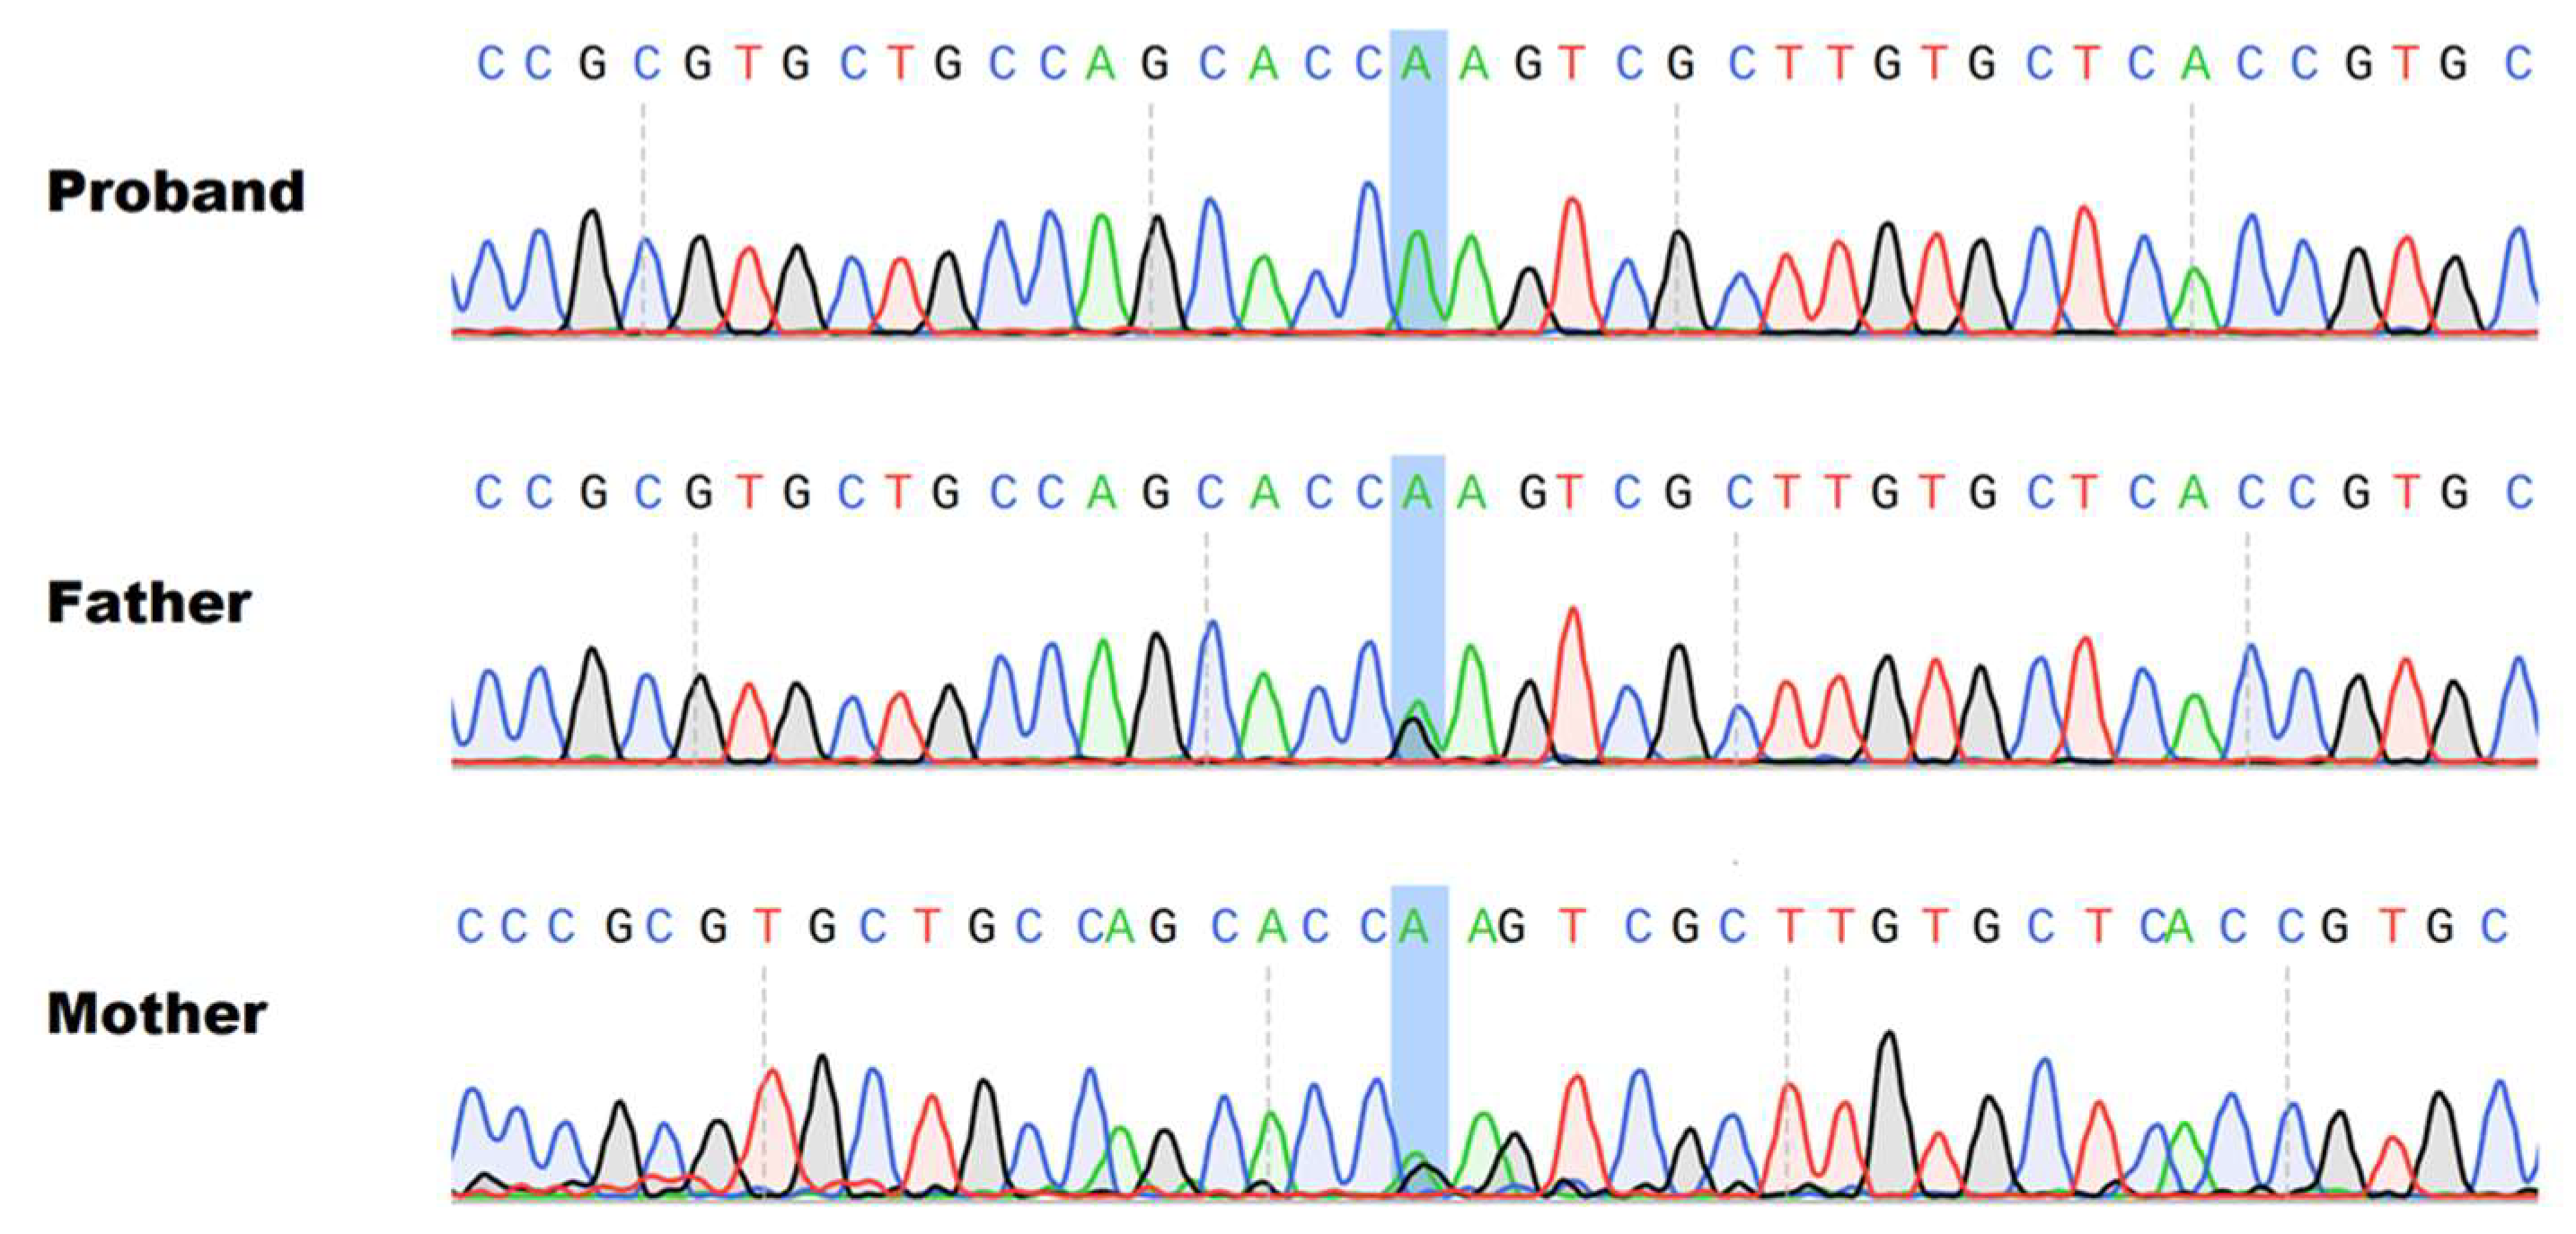

4. Results